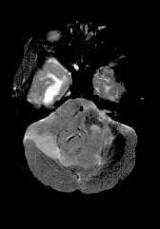

成年男性,头痛、头晕、恶心,病程二年余,结合影像图像选择最可能的诊断()A.脑膜瘤B.星形细胞瘤C.室管膜瘤D.胶质瘤E.畸胎瘤

问题 成年男性,头痛、头晕、恶心,病程二年余,结合影像图像选择最可能的诊断()

选项 A.脑膜瘤 B.星形细胞瘤 C.室管膜瘤 D.胶质瘤 E.畸胎瘤

答案 C